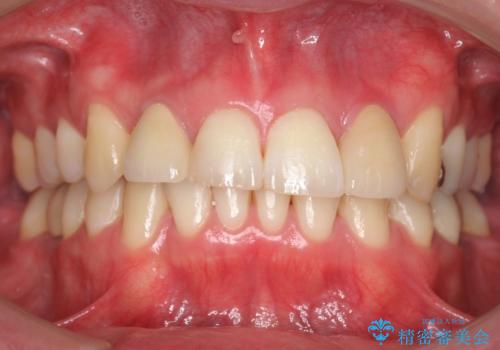

ワイヤーによる全体的ながたつきの矯正治療